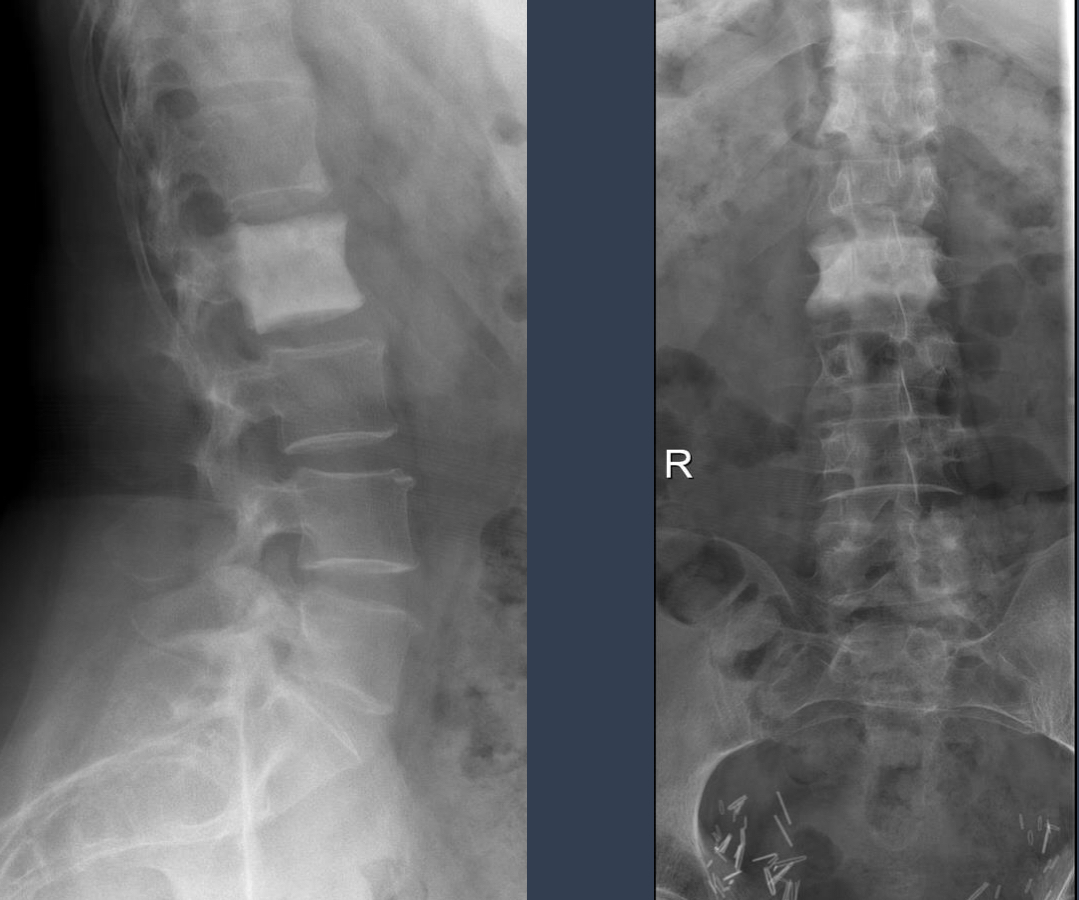

what is this phenomenon called?

and what are the 3 most common causes of it?

ivory vertebra

osteoblastic mets (multiple ivory vertebrae), paget disease (cortical thickening, expansion), lymphoma (anterior body scalloping)